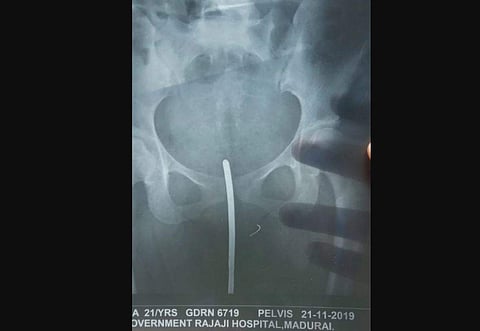

Sources at the Madurai hospital said Ramya was brought there at around 12.30 am on Thursday with the broken piece of needle intact in her pelvic bone. (Photo | EPS)

Sources at the Madurai hospital said Ramya was brought there at around 12.30 am on Thursday with the broken piece of needle intact in her pubic bone. The needle had broken while performing episiotomy (a surgical incision made at the opening of the vagina during childbirth, to aid a difficult delivery and prevent rupture of tissues), sources said.

A team of doctors, including obstetrician/gynaecologist, urologist, gastroenterologist and anaesthetist, performed an hour-long surgery and removed the broken needle.